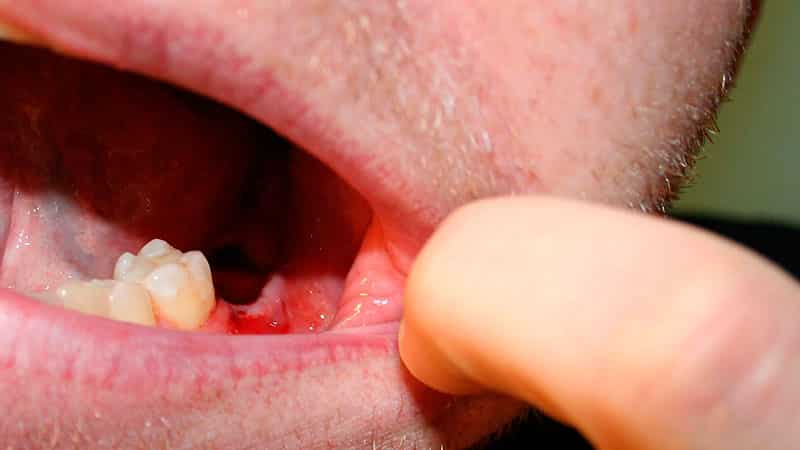

Так выглядит лунка после удаленного зуба с двумя корнями.

Как мы видим на снимке, сгусток, после операционного вмешательства стоматолога, может быть различной формы и объема — от покрывающего тонким слоем мест оставшихся от корней до значительно возвышающегося над десной комка.

Комбинированная фотография различных типов сгустков крови после удаления зубов